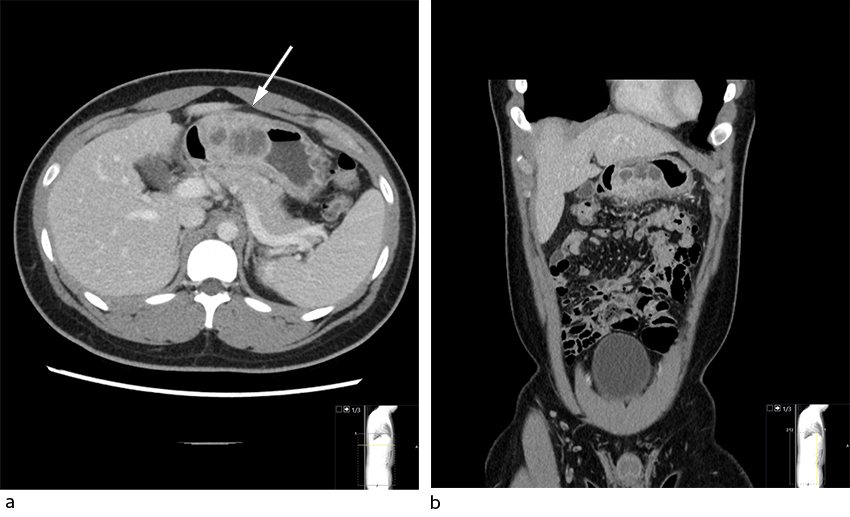

Symptomene ble oppfattet som suspekt gastritt grunnet høyt inntak av ikke-steroide antiinflammatoriske midler (NSAID), og han fikk behandling med pantoprazol 40 mg to ganger daglig peroralt. I tillegg mistenkte man infeksjon med ukjent fokus, men avventet antibiotika grunnet god allmenntilstand. På innleggelsesdag 3 steg CRP til 282 mg/L. Det ble derfor samme dag gjennomført CT abdomen (figur 1), som påviste en 60 × 35 mm intramural oppfylning prepylort i magesekken med flere lavattenuerende lokulamenter og perifer kontrastoppladning, forenlig med abscess eller malign prosess.

Gastrisk abscessdannelse er oftest lokalisert til antrum. Tilstanden affiserer menn hyppigere enn kvinner (3:1) og hyppigst i alderen 30–60 år (7). Det dominerende symptomet er epigastriesmerter. Ledsagende symptomer kan være kvalme, oppkast og feber. Smertelette fra liggende til sittende stilling (såkalte Deininger-tegn), og oppkast av rent puss er sykdomsspesifikke, men sjeldne tegn. Den vanligste mikrobielle agens er streptokokker, men også andre agens er beskrevet, blant annet stafylokokker, som illustrert her. Multimikrobiell flora er ikke uvanlig (1, 3). Abdominal CT vil ikke nødvendigvis kunne skille mellom abscess og malignitet. Endoskopisk ses en submukøs oppfylning som makroskopisk ikke kan differensieres fra gastrointestinale stromale tumorer. Abscessmistanken styrkes dersom det ved inspeksjon eller etter punksjon lekker ut puss (2). På bakgrunn av normale histopatologiske undersøkelser og komplett regress etter drenasje kunne vi konkludere med intramural gastrisk abscess.